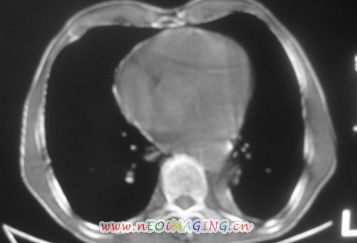

以下是引用南沙在2007-10-7 10:44:00的发言:[br]左下肺不张.[br]肺癌可能性大?

以下是引用卜一在2007-10-7 9:38:00的发言:[br]左下肺胸膜下团片影,内见含气支气管像,临近胸膜未见增厚。多考虑:1 左下肺炎症,建议消炎后复查!2 不除外肺隔离症合并感染!